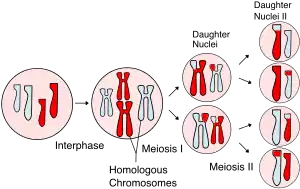

Mature cystic teratoma (MCT), affecting women in 10–20% of cases during their lifetime, is characterized by benign mature cystic teratomas—an intriguing subject in gynecological pathology.[8][3] These non-cancerous tumors, originating from at least two embryonic germ cell layers, exhibit a complex interplay of developmental pathways, stemming from singular germ cells or the complexities of meiosis I and II failure.[9][10] Internally lined with squamous epithelium and externally connected to the ovarian stroma, mature cystic teratomas contain diverse fluids such as sebaceous, serous, or mucinous.